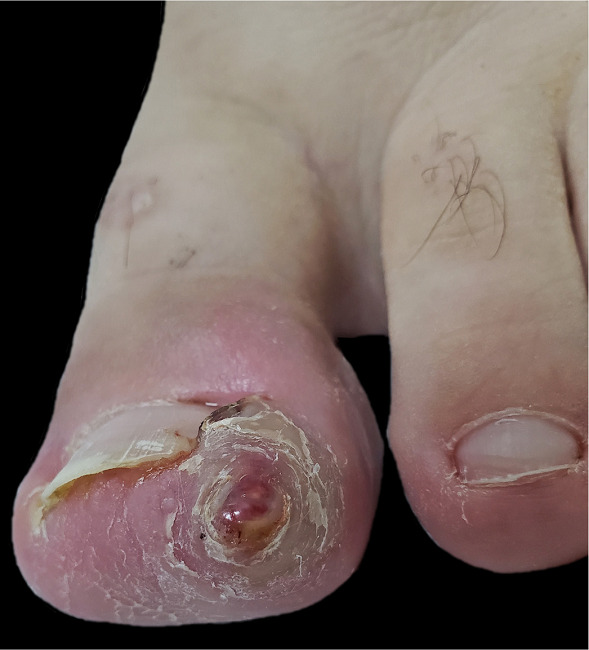

Paciente masculino, 25 anos, estudante, procurou atendimento com queixa de encravamento da unha do hálux esquerdo há mais de dois anos, acompanhado de dor intermitente, mais intensa no início do quadro. Ao exame físico, apresentava uma das dobras ungueais laterais do hálux esquerdo com acentuado aumento de volume, recobrindo boa parte da lâmina ungueal e estendendo-se ao hiponíquio; na extremidade da dobra lateral, havia uma lesão pápulo-nodular, eritematosa, recoberta por uma pequena crosta e envolta por um colarete queratótico (Figura 1). Na dobra contralateral, identificava-se um edema em menor grau.

Devido ao diagnóstico de onicocriptose nas duas dobras ungueais laterais e à formação de unha em arpão em uma delas, o paciente foi encaminhado para cirurgia. Realizamos a ressecção do excesso de tecido das dobras laterais, o que permitiu a visualização da espícula pontiaguda na porção lateral da lâmina ungueal (Figura 2); seguimos com a avulsão de uma faixa lateral da unha e finalizamos com a cauterização química (fenol 88%) do segmento lateral da matriz e da porção cruenta das dobras laterais (Figura 3). A cicatrização ocorreu por segunda intenção.